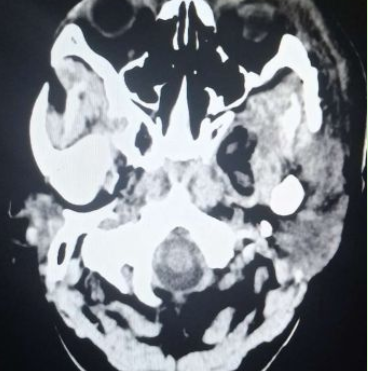

颅脑核磁示:左侧颞下窝占位。

术前核磁